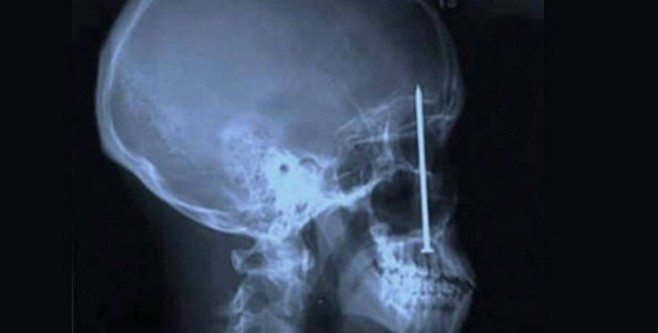

insan-ameliyat-esya-kapak13- Kafatasında bir çivi

Colorado’da bir inşaat işçisi bir gün dişçiye gitti. Dişi ağrıyan ve bulanık gördüğünü söyleyen adamın sorunu ise 20 yaş dişi değildi! Kafatasında bir çivi bulunan adam, bir hafta önce çivi makinasıyla çalışırken bir sorun yaşamıştı. Makina tepmiş, adamın ağzından içeri bir çivi göndermiş ve bu çivi de kafatasına kadar gitmişti!